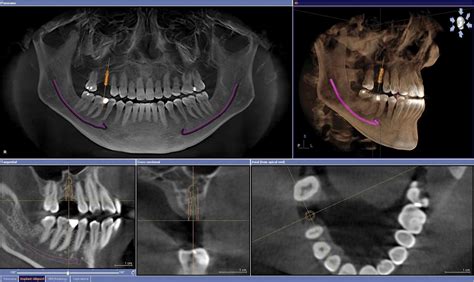

Un TAC dental, también conocido como Tomografía Axial Computarizada de la zona oral, es una técnica avanzada de imagenología que utiliza rayos X para obtener imágenes tridimensionales (3D) de los dientes, maxilares y estructuras circundantes.

A diferencia de las radiografías tradicionales, un TAC permite obtener una imagen tridimensional de la boca y maxilares, lo que representa un avance significativo en la visualización anatómica para los procedimientos odontológicos. Su principal diferencia respecto a las radiografías convencionales es, precisamente, su capacidad para obtener imágenes en 3D, lo que nos permite contar con una visión más completa y detallada de la anatomía dental y ósea de una persona.

Hoy en día, la inmensa mayoría de los TAC dentales que utilizamos son digitales. Desde el monitor, el odontólogo podrá estudiar en detalle la imagen final para establecer el diagnóstico del paciente y determinar el tratamiento a seguir.

El TAC no solo ofrece imágenes de alta resolución, sino que también permite identificar elementos clave como la densidad ósea, la ubicación precisa de nervios y vasos sanguíneos, y la relación entre las distintas estructuras de la región oral y maxilofacial. Esta información detallada es crucial para planificar tratamientos con un nivel de personalización que maximiza las probabilidades de éxito.

Con el TAC mandibular y maxilar podemos medir la anchura, altura y espacio disponible para insertar los implantes. Estudiar las estructuras óseas es esencial para determinar la posición exacta del tornillo, además de asegurar el éxito de la cirugía. La planificación de la cirugía guiada por ordenador combinada con la carga inmediata permite recuperar todos los dientes en un día.

Esta capacidad tridimensional es crucial para identificar áreas críticas que podrían no ser visibles en imágenes bidimensionales, como defectos óseos ocultos o irregularidades en la topografía ósea. El TAC permite identificar posibles riesgos antes de la cirugía, como insuficiencia ósea, proximidad a nervios o la presencia de infecciones ocultas, factores que podrían comprometer tanto el éxito del tratamiento como la seguridad del paciente.